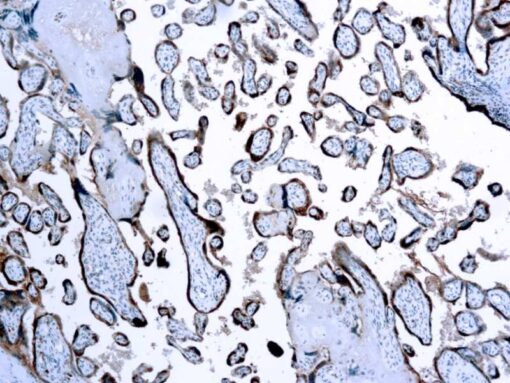

Chorionic Gonadotropin (hCG)

This antibody reacts with hCG. It stains strongly with the human placenta and placental trophoblasts.